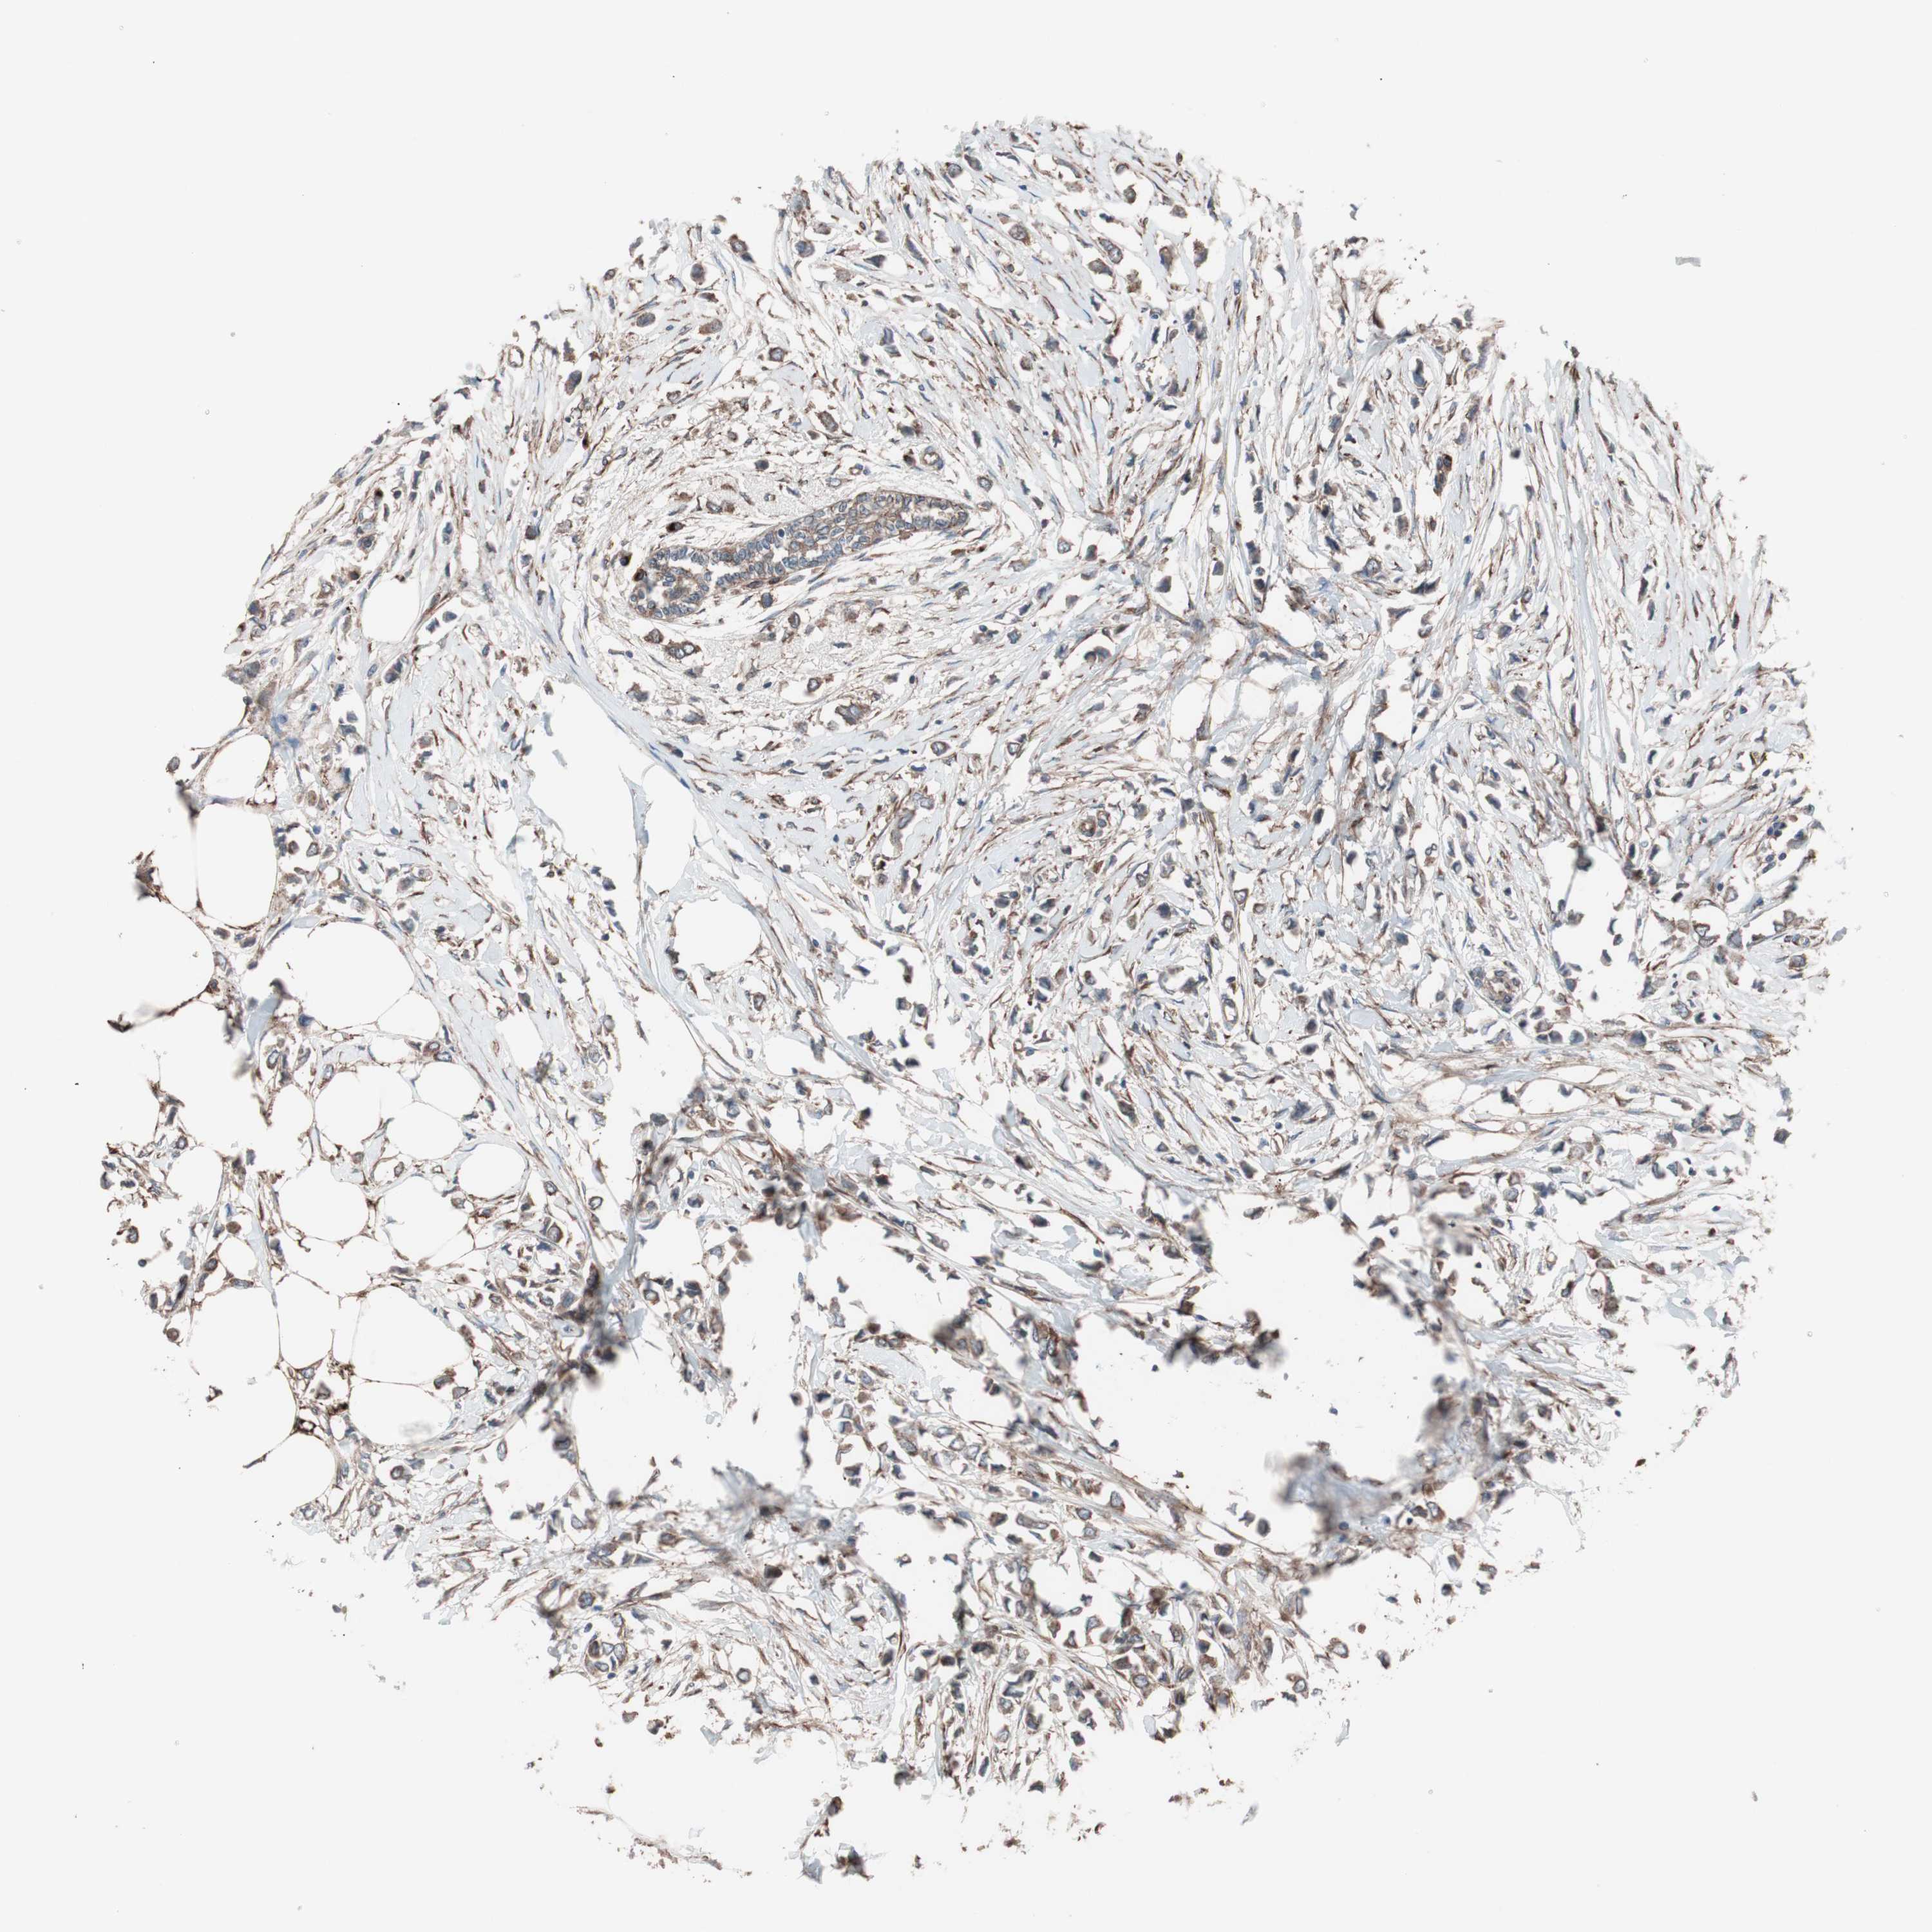

BRCA TCGA BRCA VALIDATION PROTEIN EXPRESSION

ANTIBODIES

AND

VALIDATION